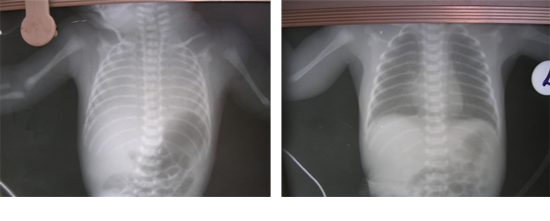

- 6. Monitoring...

7. Chest X-ray

► CPAP (4 to 7 cms) : Recessions/ CXR and SpO2

♦ CPAP Recessions/CXR